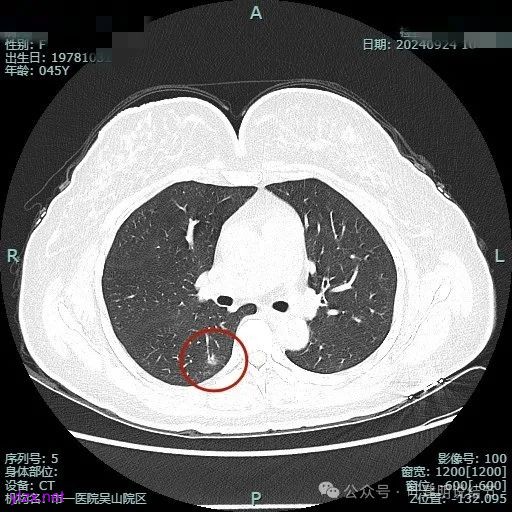

我们先来看2024年9月时的影像:

病灶1:

右下背段混合密度病灶,边上不太清爽,有片状淡磨玻璃影,实性部分密度较高。

感觉病灶有点晕征似的,表面不平,灶内不太致密。

有小血管进入,似有晕征。

离胸膜近但牵拉不明显,病灶边缘有细毛刺,较短且不太锐利。

边缘少许磨玻璃成分,血管进入明显。

瘤肺边界稍显不清。